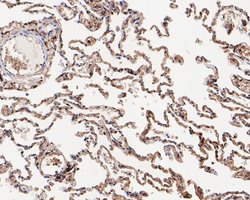

Invitrogen™ RhoGDI Polyclonal Antibody

RhoGDI Polyclonal Antibody for Western Blot, IHC (P)

| Applications | Immunohistochemistry (Paraffin), Western Blot |